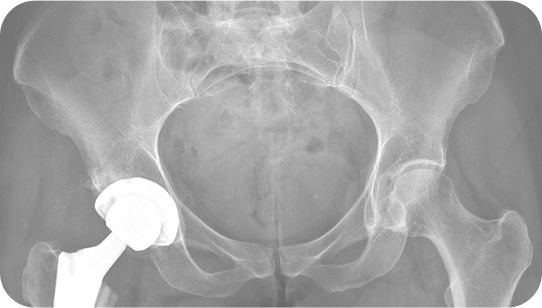

Dr. Davidovitch Specializes in Hip Surgery

• Specialist in Hip Reconstruction and Preservation.

Hip Replacement

Mako SmartRobotics™ is an innovative solution for many suffering from painful arthritis of the hip. Mako uses 3D CT-based planning software so your surgeon can know more about your anatomy to create a personalized joint replacement surgical plan.